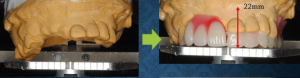

以前のブログで掲載した治療途中ケースです(「一歩づつ」2020年2月20日掲載)。あれからさらに治療が進みました(写真上段の左が術前、右が現在)。上の残っていた歯はグラグラだったり、大きく下に伸びてきてしまったりして使える歯がないと診断し抜歯しました。その直後にあらかじめ用意していた治療用義歯を装着しました。下の残存歯はだいぶすり減って大きく変形していると診断し、被せもので形態回復(現在は仮歯の状態)、右(患者さんにとっての)下臼歯欠損部はインプラントで対応という治療方針です。

石膏模型で上の歯並びを正面から見て、それぞれの歯の位置を線で結ぶと、ひん曲がったりせずほぼ直線的で、かつ顔の正中線に対して直交するのが理想的(な咬合平面)です。この患者さんの場合、術前の患者さん自身の右側(写真上では左側)が大きく下がっているのがわかります(写真下段)。写真の下方にに写っている金属の板が顔の正中面に直交する面に相当します。南カリフォルニア大学で補綴学を学ばれ仙台で開業されている阿部晴彦先生が開発されたシンラシステムという器具を使用すると、こうしたことが客観的にわかります。この情報や他の標準的なデータと合わせて、左右前後のどちら側をどの程度補正すればいいかミリ単位でわかります。型取りして作った石膏模型だけでは、いくら眺めてもこうしたことはわかりません。患者さんの顔と比較しながら何度も試行錯誤するしかありません。